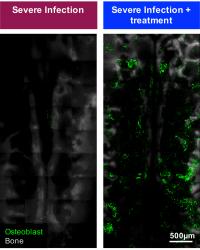

Within days of infection, blood vessels became leaky and there was a dramatic loss in bone-forming cells called osteoblasts. These changes appear strongly linked to the decline in the pool of HSCs during infection.

video: By injecting fluorescent molecules (magenta) that would normally remain in circulation and taking a series of images over time, intravital microscopy revealed that infected mice had very leaky vessels - with the contents of the bone marrow blood vessels, lined by endothelial cells (green), escaping into the surrounding tissue. The red boxes highlight the areas compared in the analysis and the white lines mark the bone. view more